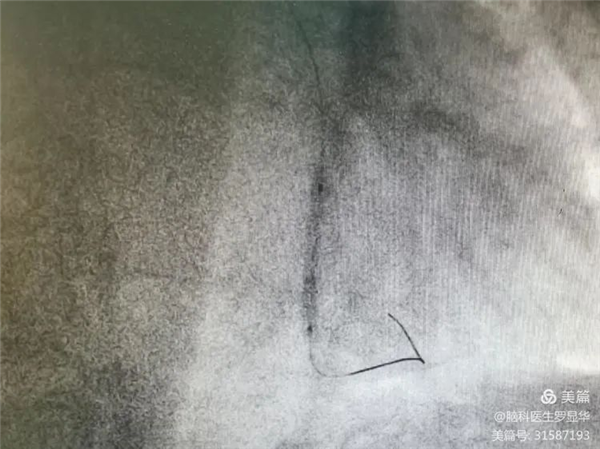

释放冠脉球扩支架